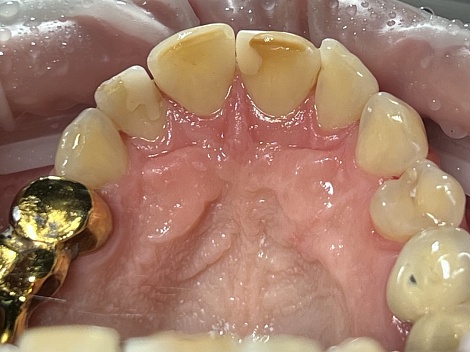

Тотальная реконструкция улыбки и функциональности зубочелюстной системы

До

После

Услуги:

Удаление зубов ,

Лечение пародонтита ,

Лечение периодонтита ,

Имплантация зубов* ,

Имплантация All-on-4 ,

Протезирование зубов ,

Протезы керамокомпозитные

Стоматология

«Все свои!» м.Крылатское